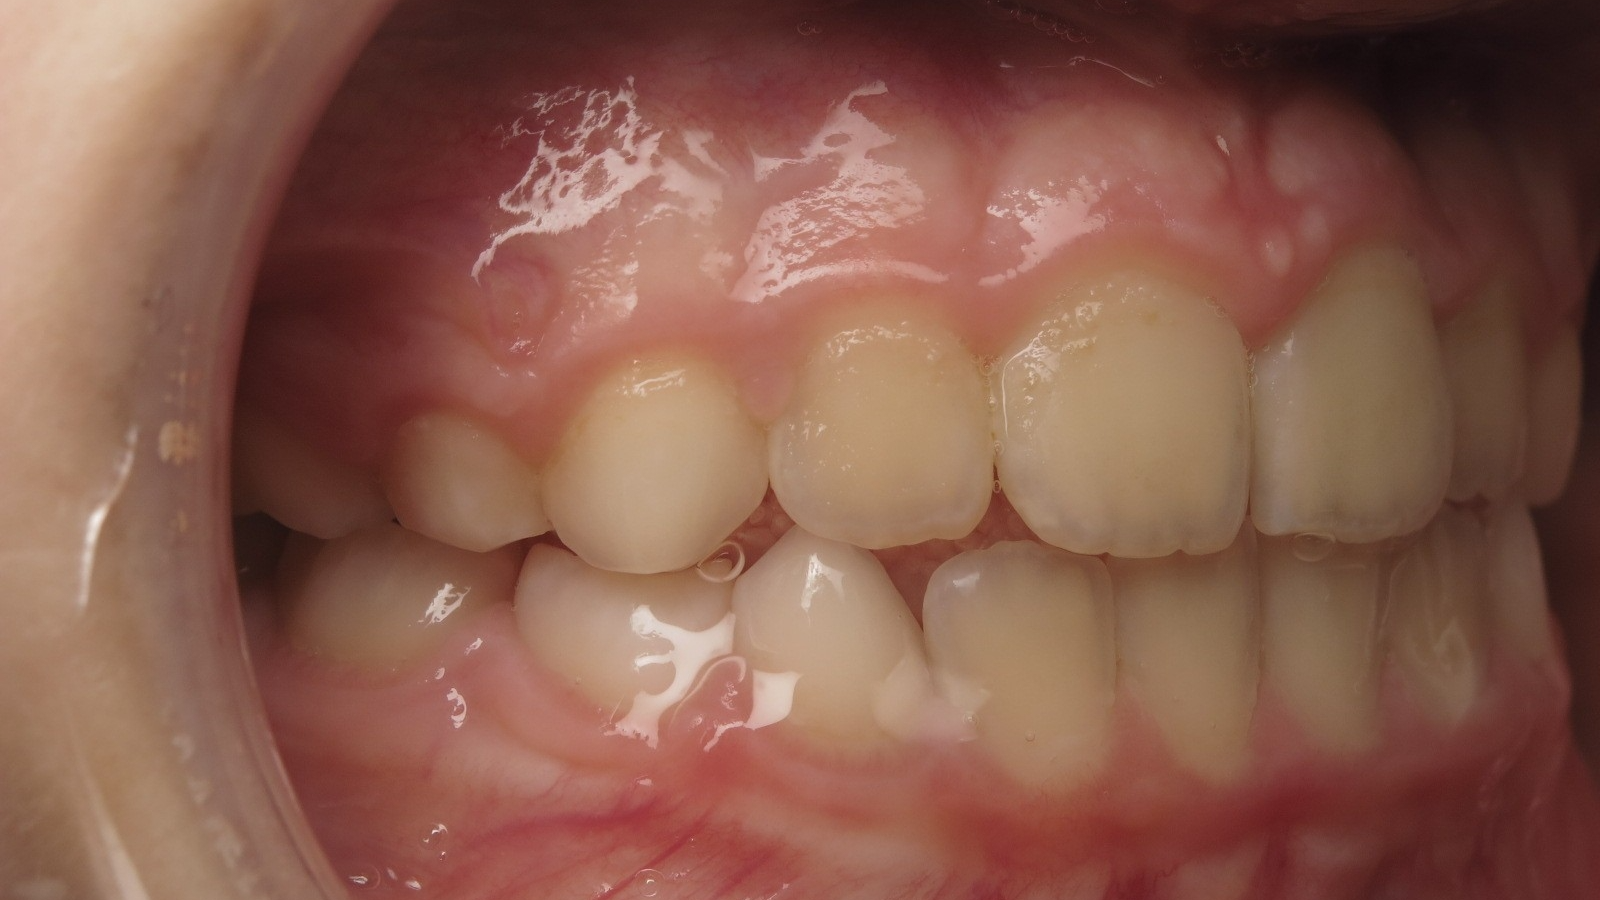

18 béance inversé droit 4 ans

inversion des dents postérieur et espace entre l'arcade du haut et du bas (béance)